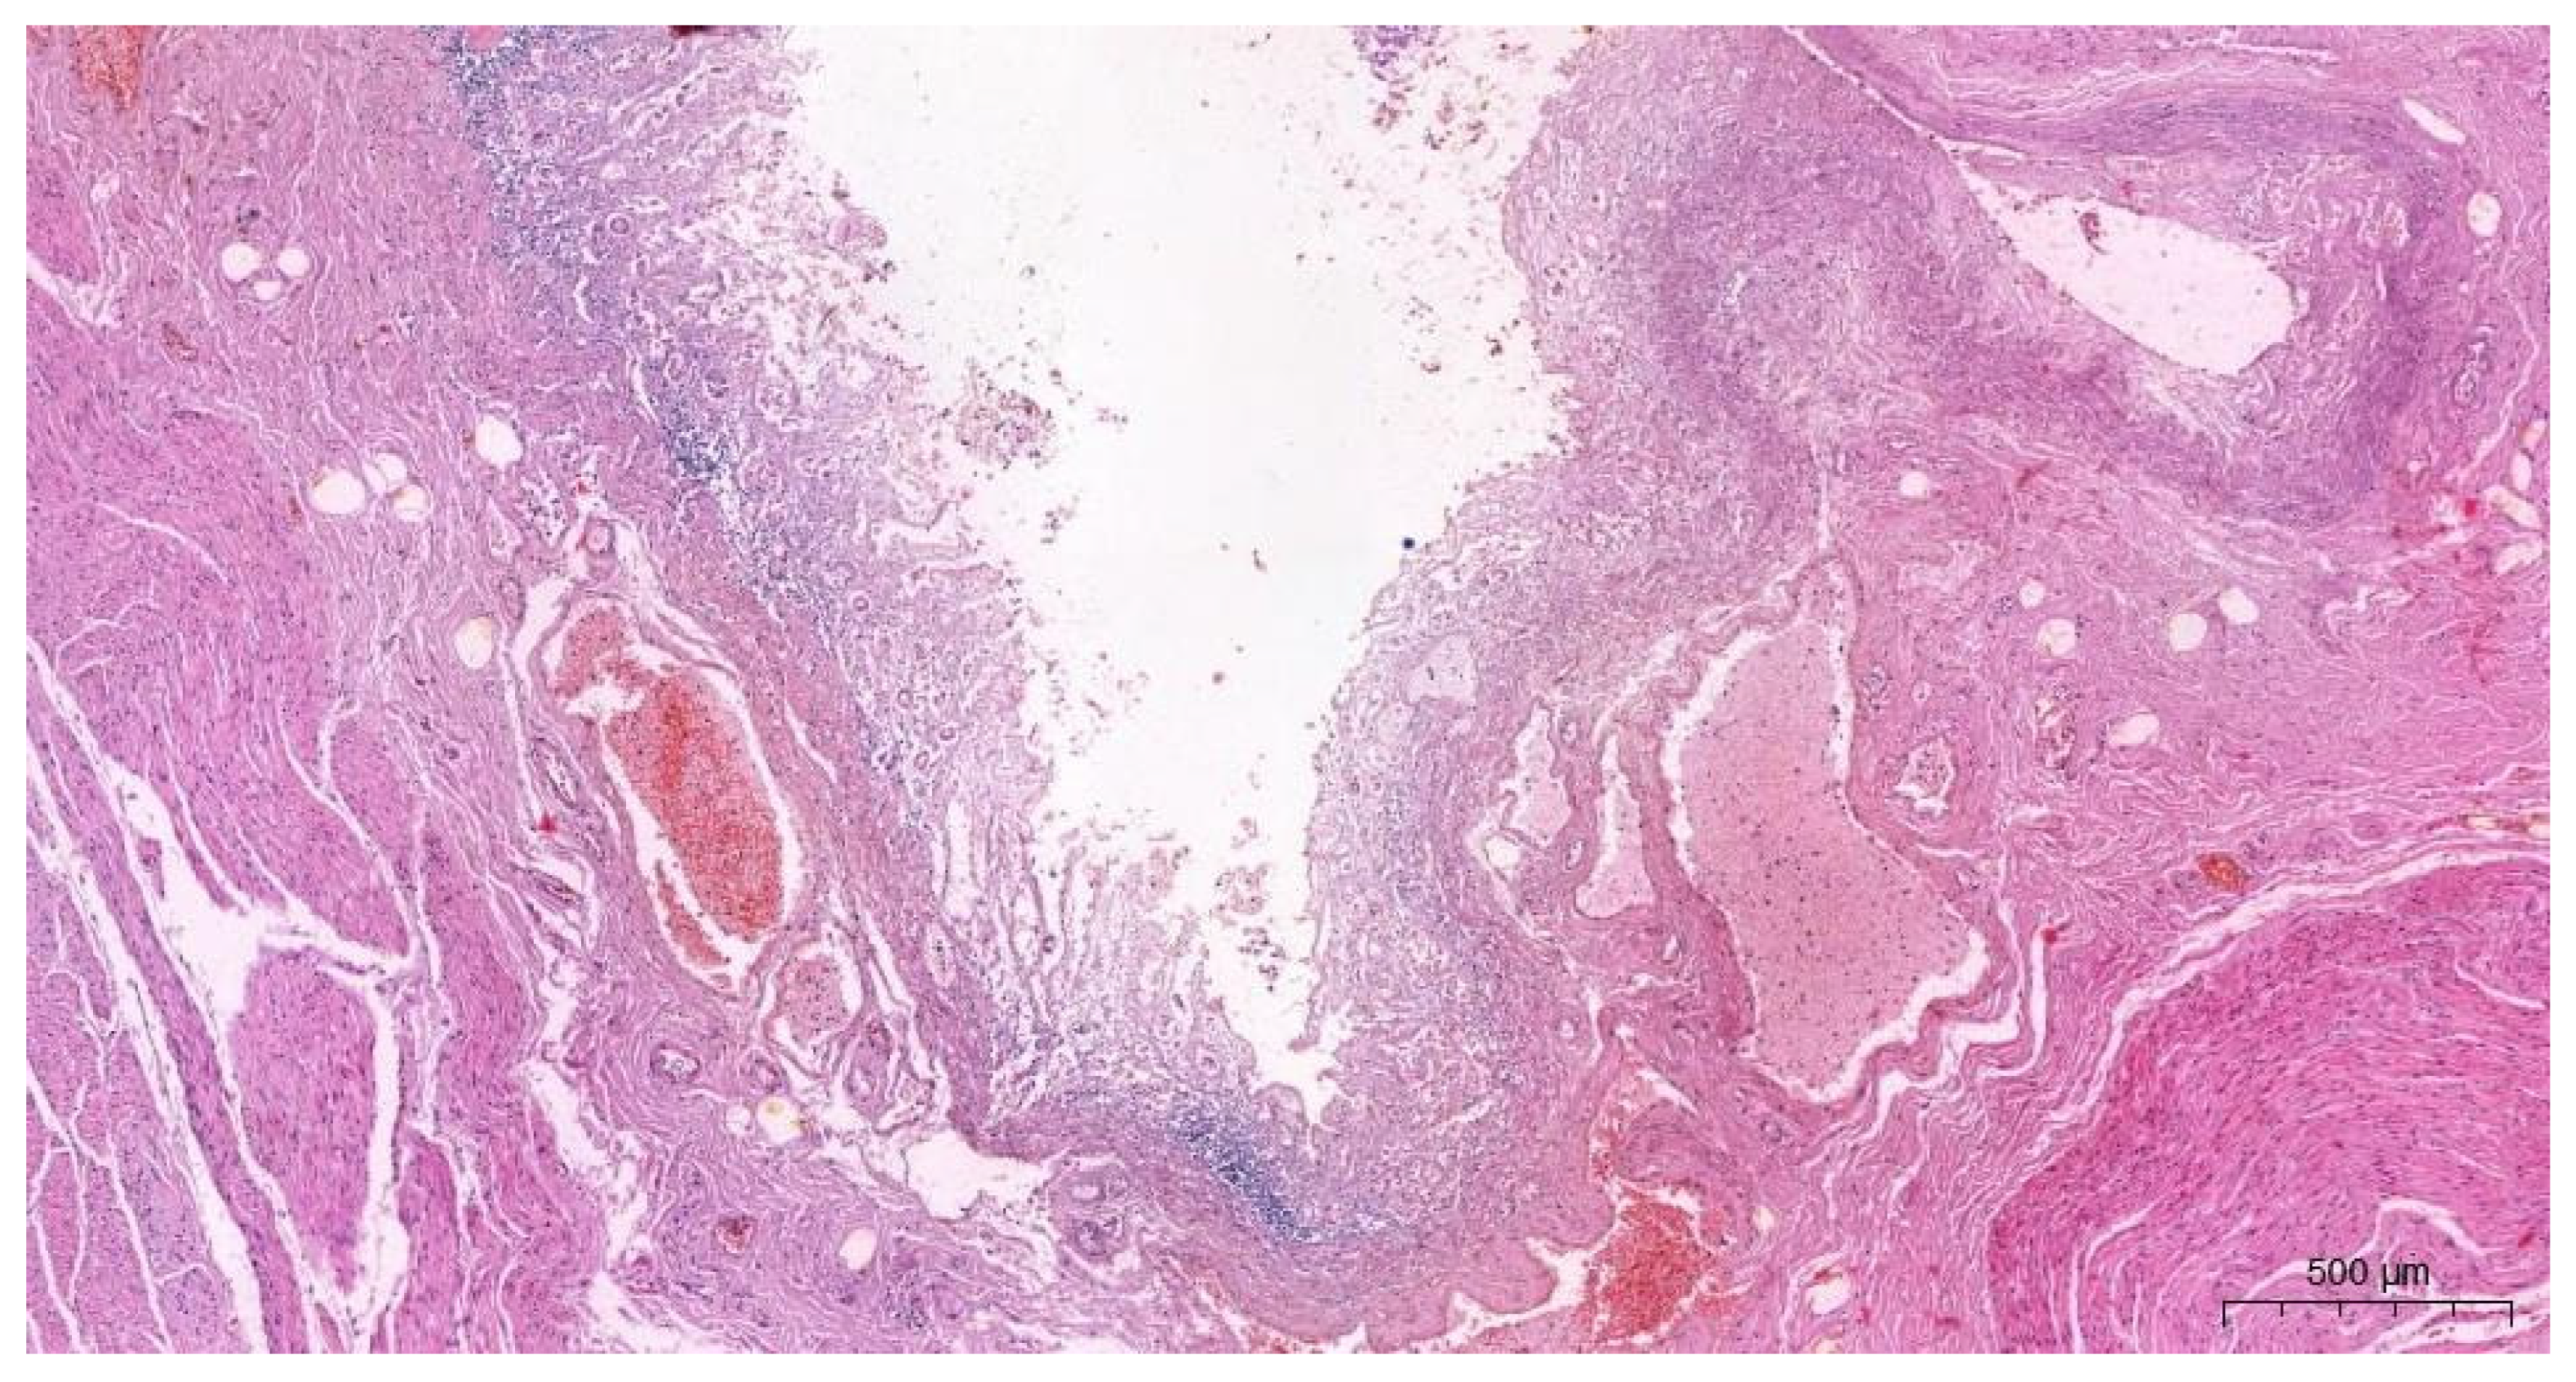

2.2.3. The Microscopic Examinations